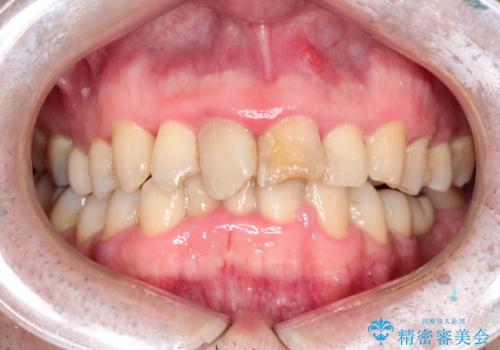

- 右下5番目の歯がしみるので診て欲しいといらっしゃった方の症例です。